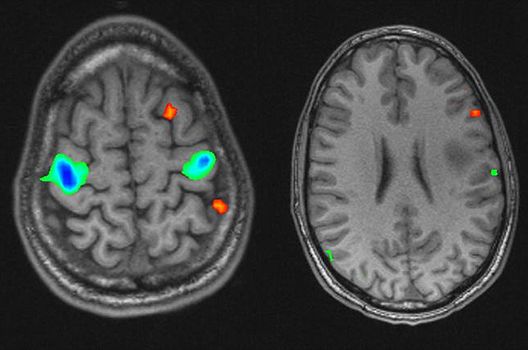

- Funktionelle Bildgebung des Gehirns (fMRT)

Die Magnetresonanztomographie (MRT) ist ein Verfahren, bei dem durch magnetische Kräfte Bilder des Körperinneren angefertigt werden. In der Neuroradiologie können manchmal kleinste Veränderungen schwere Folgen haben; daher forschen wir an der Entwicklung hochauflösender MRT-Sequenzen, mit denen diese Prozesse und auch einzelne Nervenfaserbahnen sichtbar gemacht werden können. Darüber hinaus sind bei vielen Erkrankungen des Gehirns die Blutgefäße betroffen. Daher arbeiten wir an der Neu- und Weiterentwicklung von MRT-Sequenzen zur Darstellung der Blutgefäße und zur Blutflussanalyse (sog. „Angio-MRT“). Einen besonderen Forschungsschwerpunkt unserer Klinik stellen die MR-Protonenspektroskopie und die funktionelle MRT dar, mit denen die Analyse einzelner chemischer Substanzen im Hirngewebe oder die Darstellung ausgewählter Hirnfunktionen möglich ist.